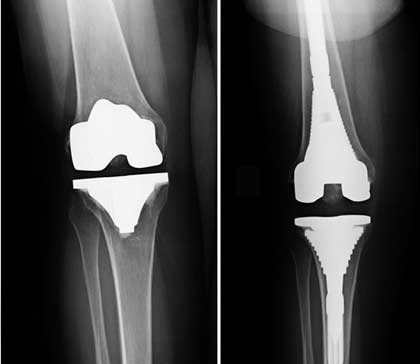

Knee replacement, also known as knee arthroplasty, is a surgical procedure to replace the weight-bearing surfaces of the knee joint to relieve pain and disability, most commonly offered when joint pain is not diminished by conservative sources and also for other knee diseases such as rheumatoid arthritis and psoriatic arthritis.